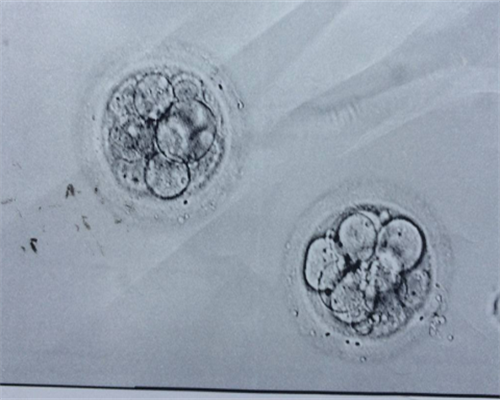

它是开始发展的。试管婴儿是试管婴儿-胚胎移植(试管婴儿-ET)技术的通用名称。它指的是从卵子中取出卵子,用精子在试管婴儿培养3到5天,然后是将已经繁殖到排卵期或胚泡期的胚胎移植到子宫腔中以使整个植入过程成为胎儿。使用试管婴儿技术出生的婴儿被称为试管婴儿,这些婴儿也在母亲的子宫中生长。